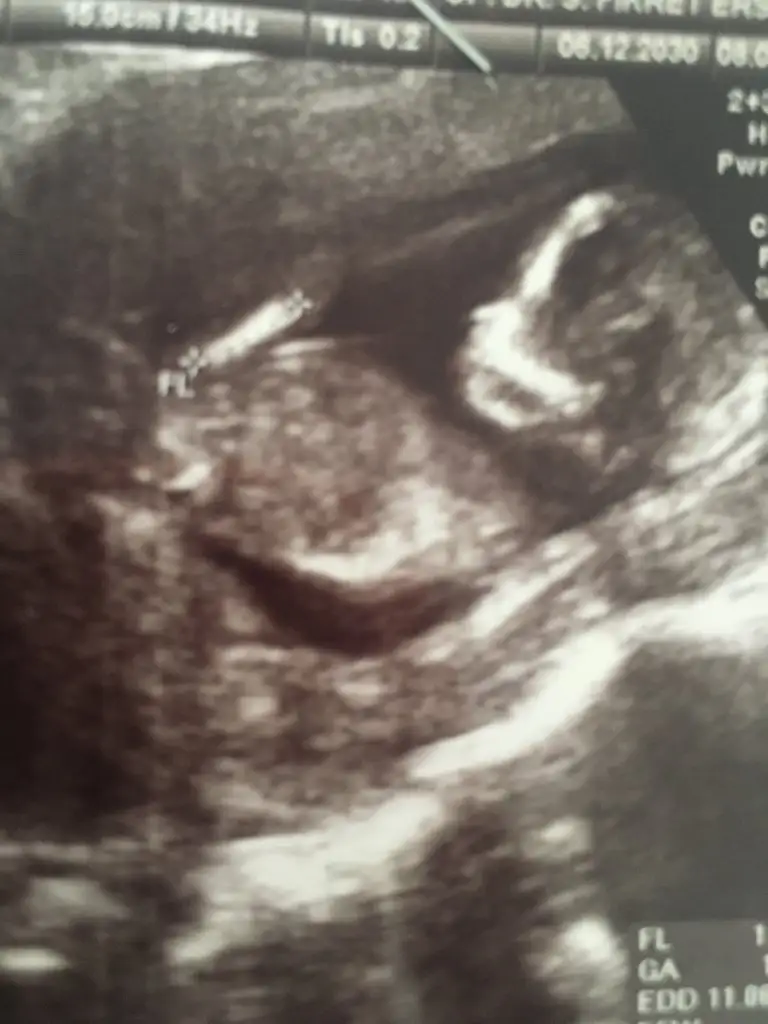

Artık birdahaki kontrole gidinceAçısı dik değilpopoya paralel iniyor başka USG varsa paylaşın

Erkek gibi benceEki Görüntüle 2752318 @Ikra meyra merhabalar bir tahminde bulunurmusunuz 12+6![]()

Kız görünüyorEki Görüntüle 2752318 @Ikra meyra merhabalar bir tahminde bulunurmusunuz 12+6![]()

Bu kaç haftalik erkek görünüyor en iyi 11 12 13 haftalar olmalıBir önceki gittiğimizden bu var![]()